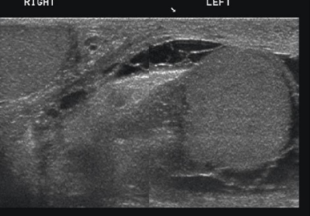

what is the buddy sign?

showing both testicles with the same color box and settings

when evaluating epididymo-orchitis the ___________________ sign is very important

buddy sign